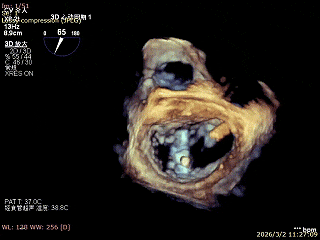

患者为房间隔缺损术后合并功能性二尖瓣反流(FMR),病变位于二尖瓣2区偏3区,因既往ASD修补史(可降解房间隔缺损封堵器),致房间隔穿刺区域存在瘢痕粘连、穿刺难度增加,于靠下靠后位置穿刺,避开房间隔缺损封堵伞,其余病变解剖结构相对简单;术前制定手术策略,拟使用1把XTR行二尖瓣修复,术中克服瘢痕粘连难点成功完成房间隔穿刺,穿刺点距二尖瓣瓣环平面3.1cm,将XTR‑CDS送入左心房,通过”A”旋钮旋转180度借高度,LVOT切面夹子严重Huge,使用”+”旋钮一键消除Huge,通过操控“M”旋钮将二尖瓣夹精准定位于2区正上方,完成弹道测试及Orientation调整后,于2区将夹子送入左心室,顺利捕捞并夹持瓣叶后缓慢闭合夹臂;TEE检查示二尖瓣反流充分降低至微量,二尖瓣双孔组织桥稳定,跨瓣压差2mmHg,肺静脉逆流明显改善,手术安全顺利结束。

释放夹子

双孔组织桥稳定

3D enface反流充分降低

术后平均跨瓣压差2mmHg